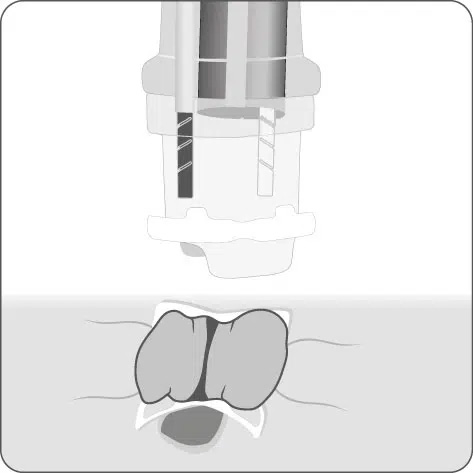

Positionsermittlung

Die korrekte Positionierung der BARS® Anchor ist entscheidend für eine erfolgreiche Behandlung.

- Mit einer gedachten Mittellinie die Anastomose in zwei Hälften teilen.

X = Austrittspunkt Endoskoparbeitskanal - Die Anchor knapp unterhalb der Mittellinie platzieren.

• = BARS® Anchor Black, • = BARS® Anchor Silver. - Der Kalibrierballon (•) definiert das Restlumen im gegenüberliegenden Halbkreis.

Platzieren des Kalibrierballons in der Anastomose. Schrittweises Einziehen des Gewebes in die BARS® Applikationskappe, mit abwechselnden Zugbewegungen.

Sicherstellen, dass das Gewebe symmetrisch in der Kappe positioniert ist. Platzieren des BARS® Clips durch Drehen des Handrads.

Zurückziehen der Instrumente und Inspektion der Clip-Applikationsstelle.